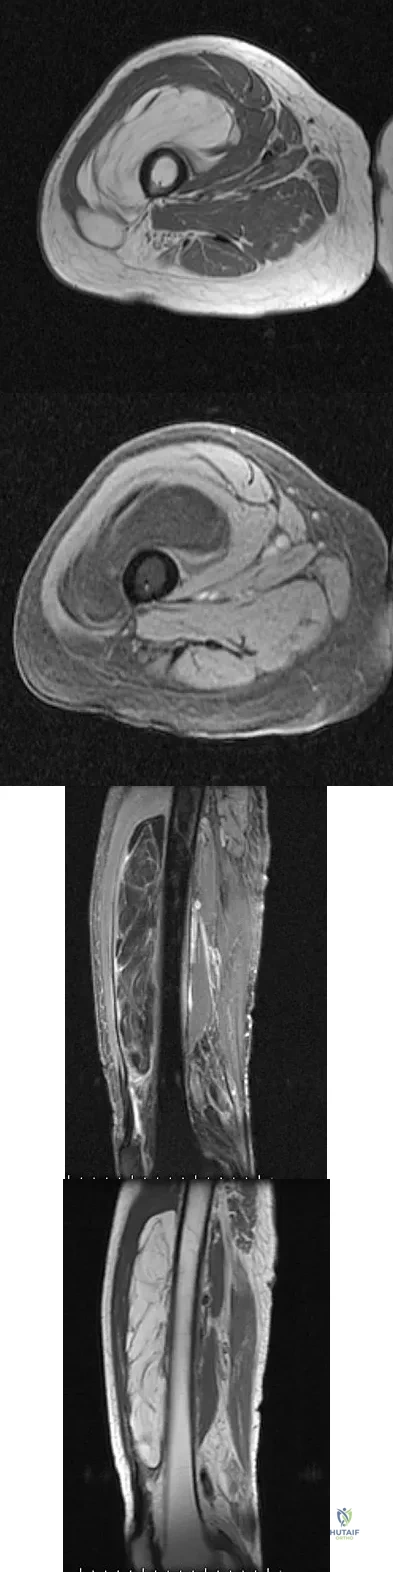

Question 20

A 19-year-old man has had pain and swelling in his left forearm for the past 8 months. Laboratory studies show a mildly elevated WBC count and erythrocyte sedimentation rate. Radiographs are shown in Figures 58a and 58b, a CT scan is shown in Figure 58c, and T1- and T2-weighted MRI scans are shown in Figures 58d and 58e, respectively. A biopsy specimen is shown in Figure 58f. Immunohistochemistry demonstrates that the lesion is negative for leukocyte common antigen (CD34). What is the most common cytogenetic translocation associated with this lesion?